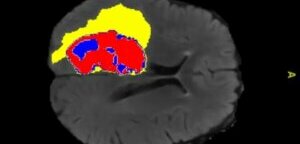

В России создали нейросеть для оценки развития мозга младенцев

Анализ МРТ-снимков позволит ускорить диагностику патологий развития центральной нервной системы, в том числе ДЦП.